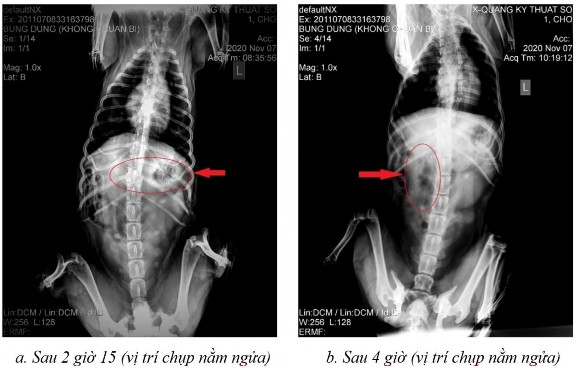

Phụ lục 5.2. Hình ảnh X-quang chó 3 ở thời điểm (a) sau 2 giờ 15 ở vị trí nằm ngửa, (b) sau 4 giờ ở vị trí nằm ngửa, (c) sau 7 giờ ở vị trí nằm ngửa và (d) sau 9 giờ ở vị trí nằm ngửa